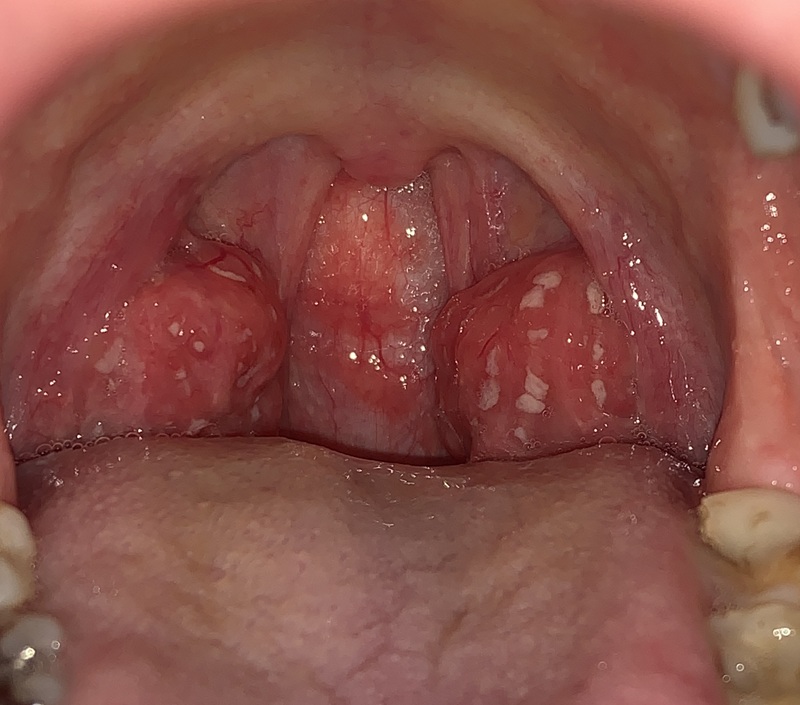

咽頭炎・滲出性扁桃炎 アデノウイルスによる 画像太田こどもとアレルギークリニック 新潟県長岡市の小児科・アレルギー科・内科。